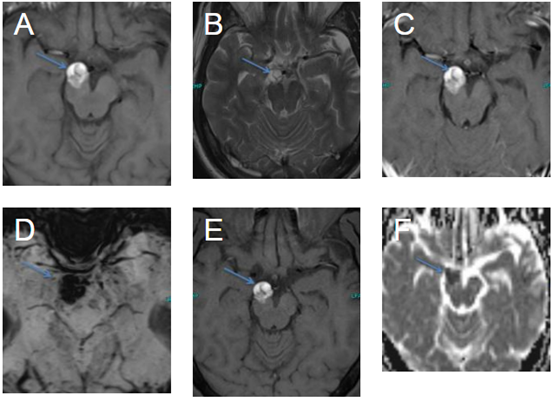

50岁男性,头痛

。影像学见下:

右脑脚(箭头)有轴内外生性病灶。T1WI(A)为高信号,T2WI(B)为高信号伴内间隔,T1WI(C)造影后未见增强(减影未显示)。病灶在BLOD图(D)上明显晕状,在脂肪饱和的T1WI(E)上无信号抑制。在ADC图上可以看到较低的值,但是在存在晕状伪影的情况下,价值可能会因此降低(F)。